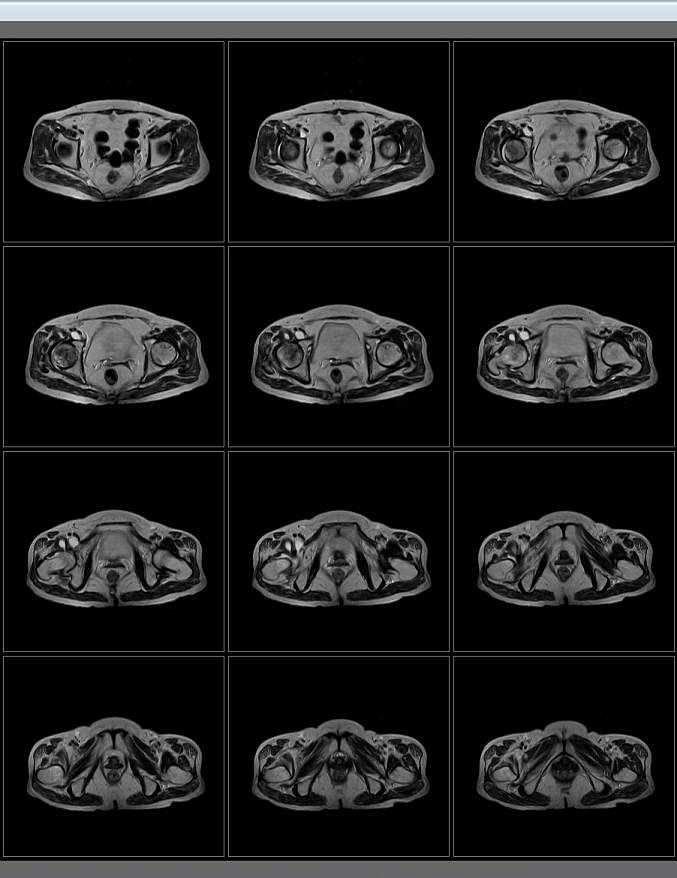

Body Imaging

La Body Suite è specializzata in esami clinici addominali e total body.